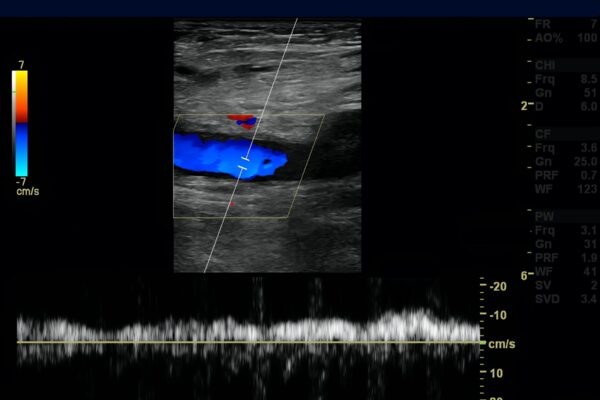

Duplex- und Dopplersonographie

Duplex- und Dopplersonographien sind spezielle Ultraschalluntersuchungen, mit denen Arterien und Venen, also Blutgefässe, beurteilt werden können. Der Schallkopf sendet Wellen in einer bestimmten Frequenz aus, die Wellen werden von den Blutkörperchen und den Gefässwänden in einer veränderten Frequenz reflektiert. Diese Veränderungen der Frequenzen hängen u.a. von der Bewegung der Blutkörperchen ab. Dadurch kann die Richtung des Blutflusses und die Fliessgeschwindigkeit des Blutes bestimmt werden. Dem Arzt ist es dadurch möglich, Einengungen (Stenosen) oder Verschlüsse von Blutgefässen zu erkennen. Die Methode ist völlig risikofrei und eignet sich zur Untersuchung sämtlicher Blutgefässe am Hals, an den Extremitäten (Arme und Beine) sowie im Bauchraum.

- Venenthrombosen an den Beinen (Venenverstopfung durch Blutgerinnsel)